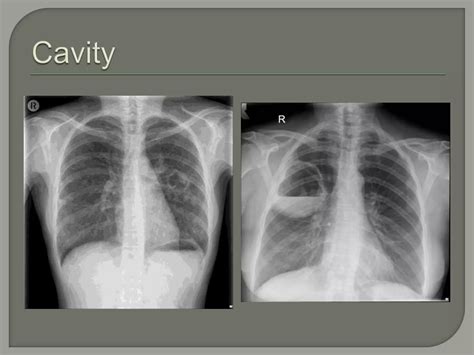

At its core, Bullous Lung Disease is a pulmonary disorder defined by the presence of at least one large air-filled space (a bulla) within the lung, which has a diameter of more than one centimeter. These bullae are essentially damaged air sacs (alveoli) that have merged and lost their elastic properties. Over time, these pockets trap stale air, preventing the lungs from effectively exchanging oxygen and carbon dioxide, which leads to feelings of shortness of breath and chronic fatigue.

While often associated with emphysema, bullae can develop through various mechanisms. The lung tissue essentially loses its internal architecture, leading to areas of over-inflation. When these areas become large enough to compress healthy surrounding tissue, the condition is referred to as giant bullous emphysema, or Vanishing Lung Syndrome, in extreme cases.

Medical professionals categorize the severity of the disease based on the size of the bullae and the impact they have on the patient’s respiratory function. The table below outlines how these bullae are typically classified in clinical practice.

Classification Bulla Size Clinical Impact

Small Bullae 1–5 cm Minimal symptoms; usually stable.

Large Bullae 5–10 cm Noticeable breathlessness; potential compression.

Giant Bullae > 10 cm Severe, requiring urgent evaluation and potential surgery.